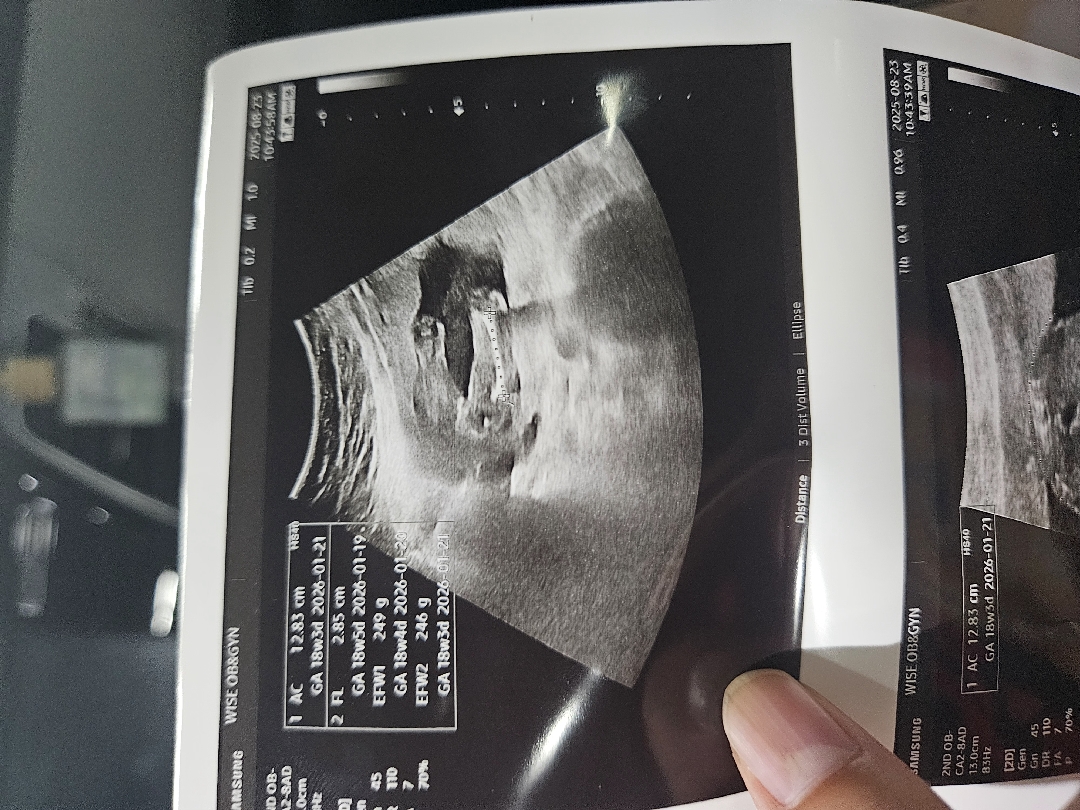

17주6일 성별 반전 없겠죠?

선생님이 사진 찍어주셨는데 이정도면 반전 없겠죠??? 아들 둘 엄마에요ㅠㅠㅠㅠㅠㅠㅠㅠㅠ 분명 며칠전까지 삼각점 봤다가 4일만에 사라졌어요ㅠㅠㅜㅠㅠㅠ 딸 맞겠죠?